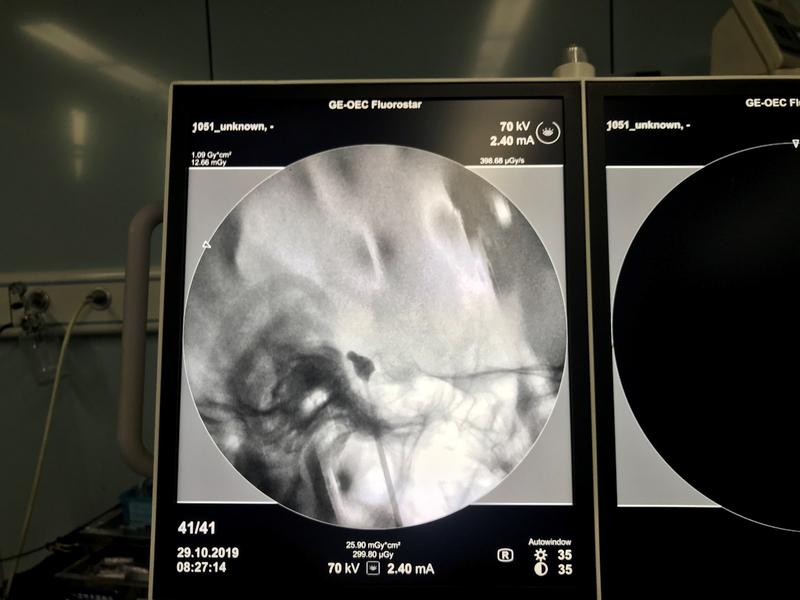

10月28日上午11:00,神經(jīng)外科成功為一名77歲男性實施“三叉神經(jīng)痛微球囊壓迫術(shù)”(PBC),這是我院神經(jīng)外科首例采用PBC手術(shù)治療三叉神經(jīng)痛,手術(shù)壓迫4分鐘患者疼痛消失。目前該項技術(shù)全市領(lǐng)先,此舉標志著我院神經(jīng)外科醫(yī)療技術(shù)水平再上新臺階。

三叉神經(jīng)半月節(jié)球囊壓迫術(shù)(PBC),指在影像引導(dǎo)下通過“微球囊”對半月節(jié)進行短暫壓迫,從而阻斷痛覺神經(jīng)傳導(dǎo),最終達到祛除面痛的治療效果。與開顱手術(shù)相比,球囊壓迫術(shù)不僅整個手術(shù)創(chuàng)面僅為一個針眼,更具有手術(shù)時間短、費用低、創(chuàng)傷小、風(fēng)險低、術(shù)后恢復(fù)快、療效確切等優(yōu)勢。